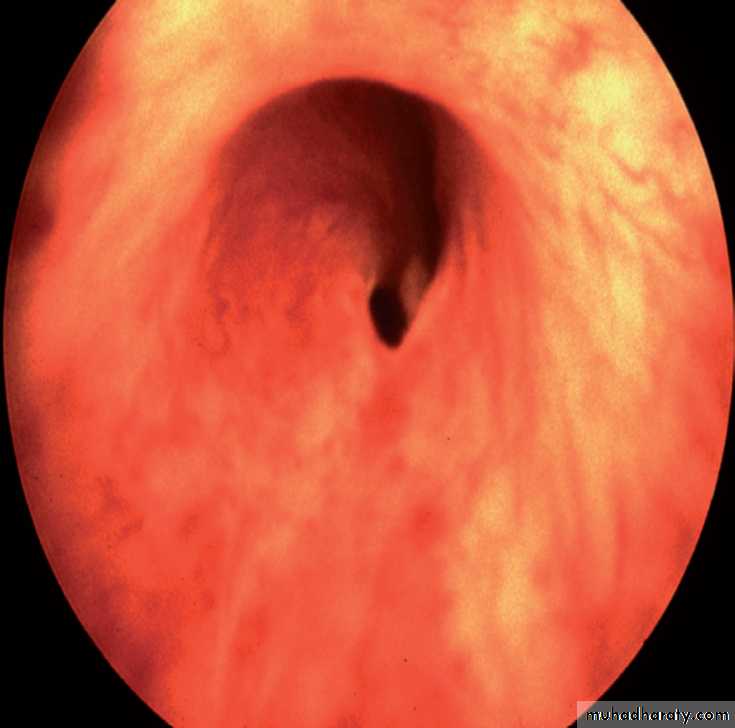

Cystoscope: by visulization of the valve

PUV (cystoscope)